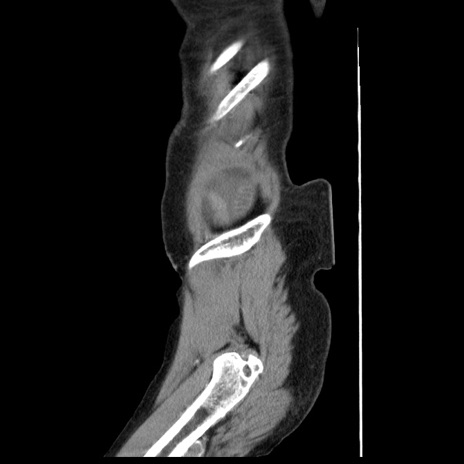

横断像